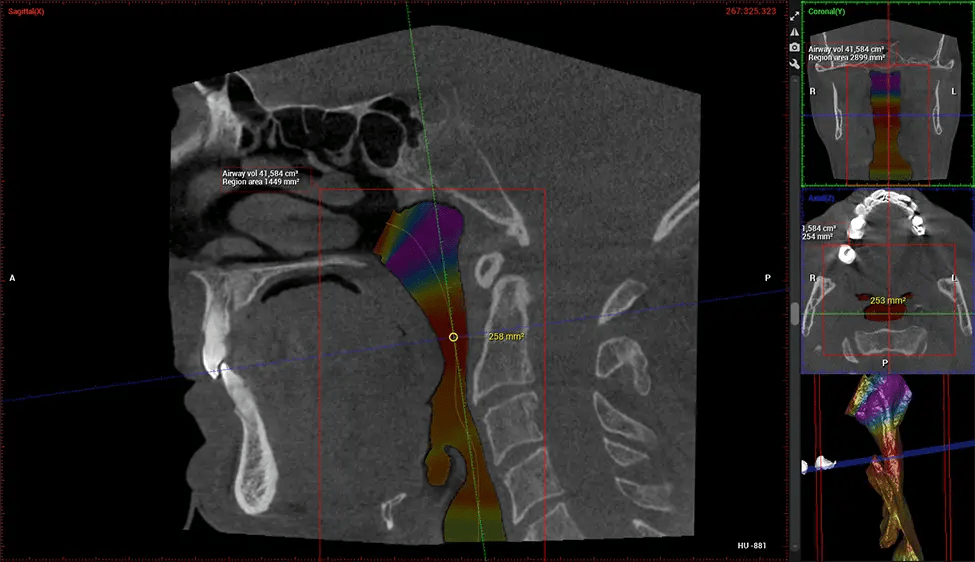

Cone Beam Computed Tomography (CBCT) is an advanced imaging technique used in dentistry and maxillofacial surgery to obtain detailed 3D images of the oral and maxillofacial structures. At Dr G Dental Studio, our CBCT scanners utilize a cone-shaped X-ray beam and a specialized detector to capture images from different angles. A computer then combines these images to create a 3D representation of the patient’s oral anatomy.

This 3D scan, called cone beam computed tomography, gives your dentist a more complete image of your oral anatomy and disease processes than a traditional X-ray. Unlike conventional X-rays, which capture a 2D image of your mouth from various angles, a 3D scan takes multiple digital X-rays for one image. It provides a complete view of your jaw, teeth, nerves, and soft tissues. This enhanced view allows dentists to detect minor issues not visible in traditional 2D scans, such as impacted wisdom teeth or bone fractures in the sinus cavity.

After the scanning process, the captured X-ray images are processed by the CBCT software, which applies algorithms to reconstruct a detailed 3D image of the scanned area. The software compiles these individual X-ray images and creates a digital 3D representation of the patient’s anatomy. The reconstructed 3D CBCT image can be viewed and analyzed by the dentist or radiologist. This image can be manipulated, rotated, and zoomed in or out to examine specific structures and evaluate the patient’s condition.